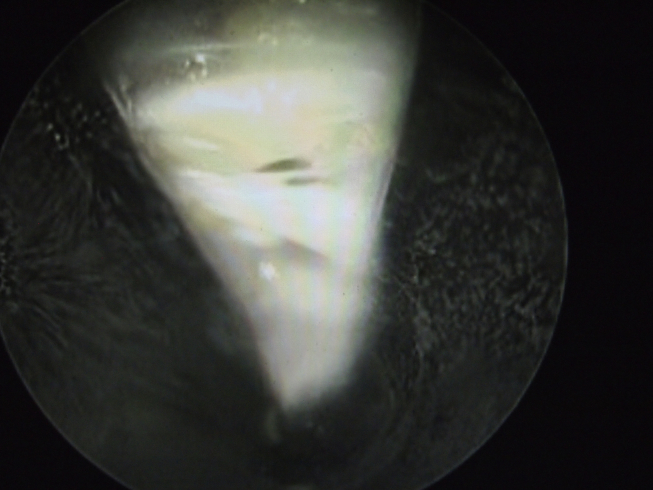

Fig. 3.

The transverse intermetatarsal ligament (TIML) was visualized with the slot of the cannula facing the 12 o'clock dorsal position.